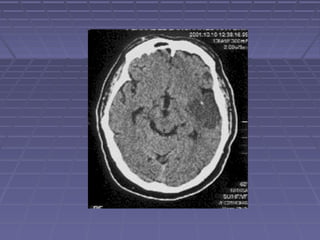

 TAC de cráneoTAC de cráneo si: persisten o aumentan lassi: persisten o aumentan las

manifestaciones clínicas, se sospechamanifestaciones clínicas, se sospecha

herniación, persiste la fiebre.herniación, persiste la fiebre.

 TC: hidrocefalia, lesiones vasculares,TC: hidrocefalia, lesiones vasculares,

tuberculomastuberculomas